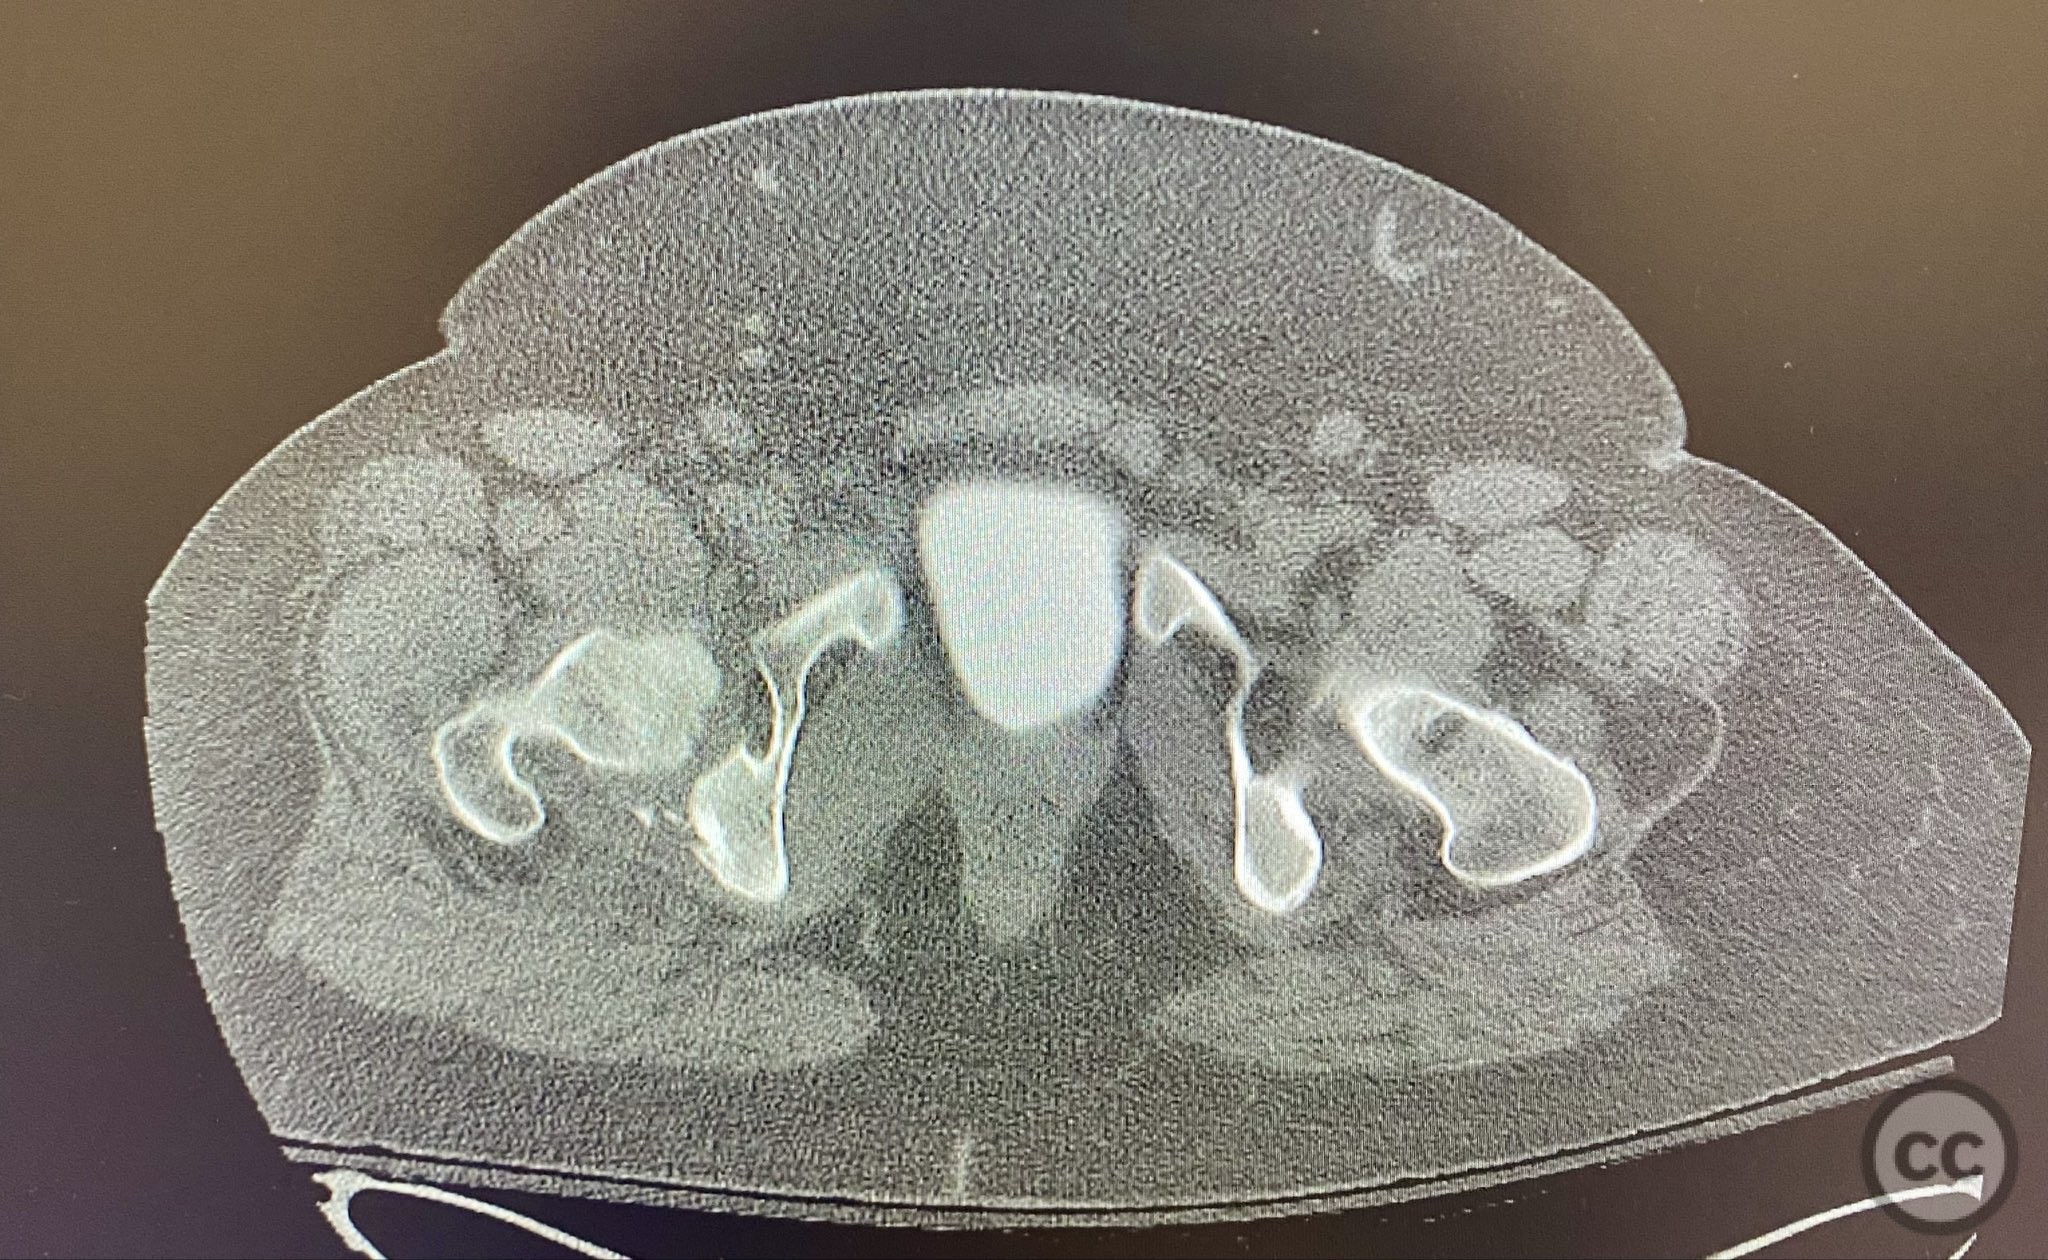

Clinical and radiological findings:  A high-speed motor vehicle collision resulted in a closed transverse acetabular fracture with associated comminuted posterior wall (PW) fracture-dislocation. The femoral head exhibited impaction and comminution, with local cancellous bone crushed and the femoral head itself also sustaining compressive injury from the denser acetabular bone. Neurovascular examination was unremarkable. Initial CT imaging delineated the acetabular fracture planes, displacement, comminution of the posterior wall, femoral head impaction, and absence of soft tissue attachment to the caudal PW fragment.